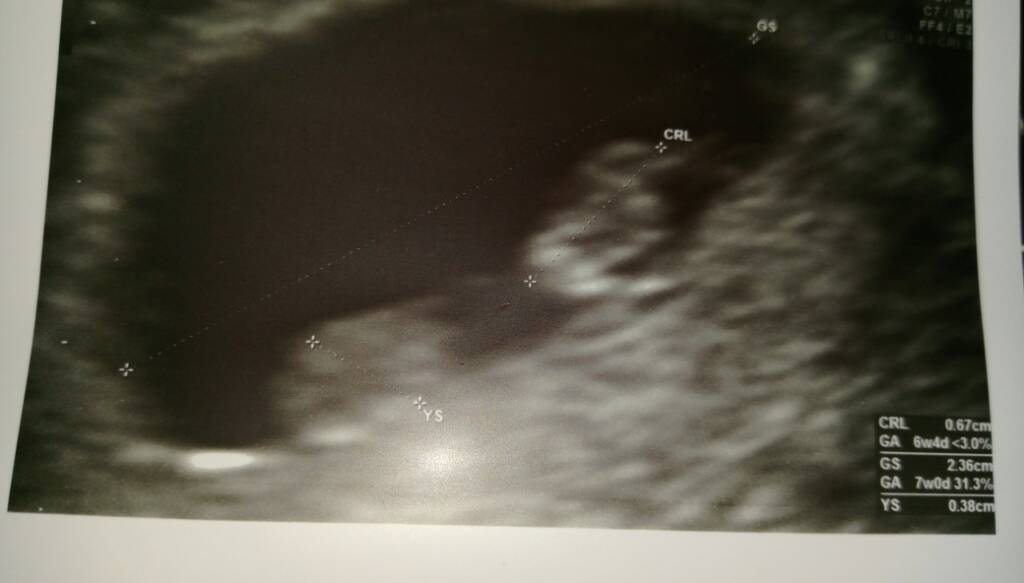

GratulacjeMoja fasolka [emoji173] Zobacz załącznik 830716

O jakie zblizenie [emoji5] Sliczna [emoji3]Moja fasolka [emoji173] Zobacz załącznik 830716